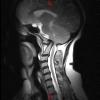

Paciente con cuadro aparentemente de inicio brusco consistente en torpeza de hemicuerpo izquierdo de predominio crural. Asocia trastorno disestésico en extremidades izquierdas y dudosa alteración de la sensibilidad térmica en el lado derecho del cuerpo....

Caso completo | PDF

Neurología: Patología de raquisEtiología: Trauma | OtrosDiagnóstico final: Mielopatía cervical alta por sublimación atlantoaxoideaNivel de certeza: